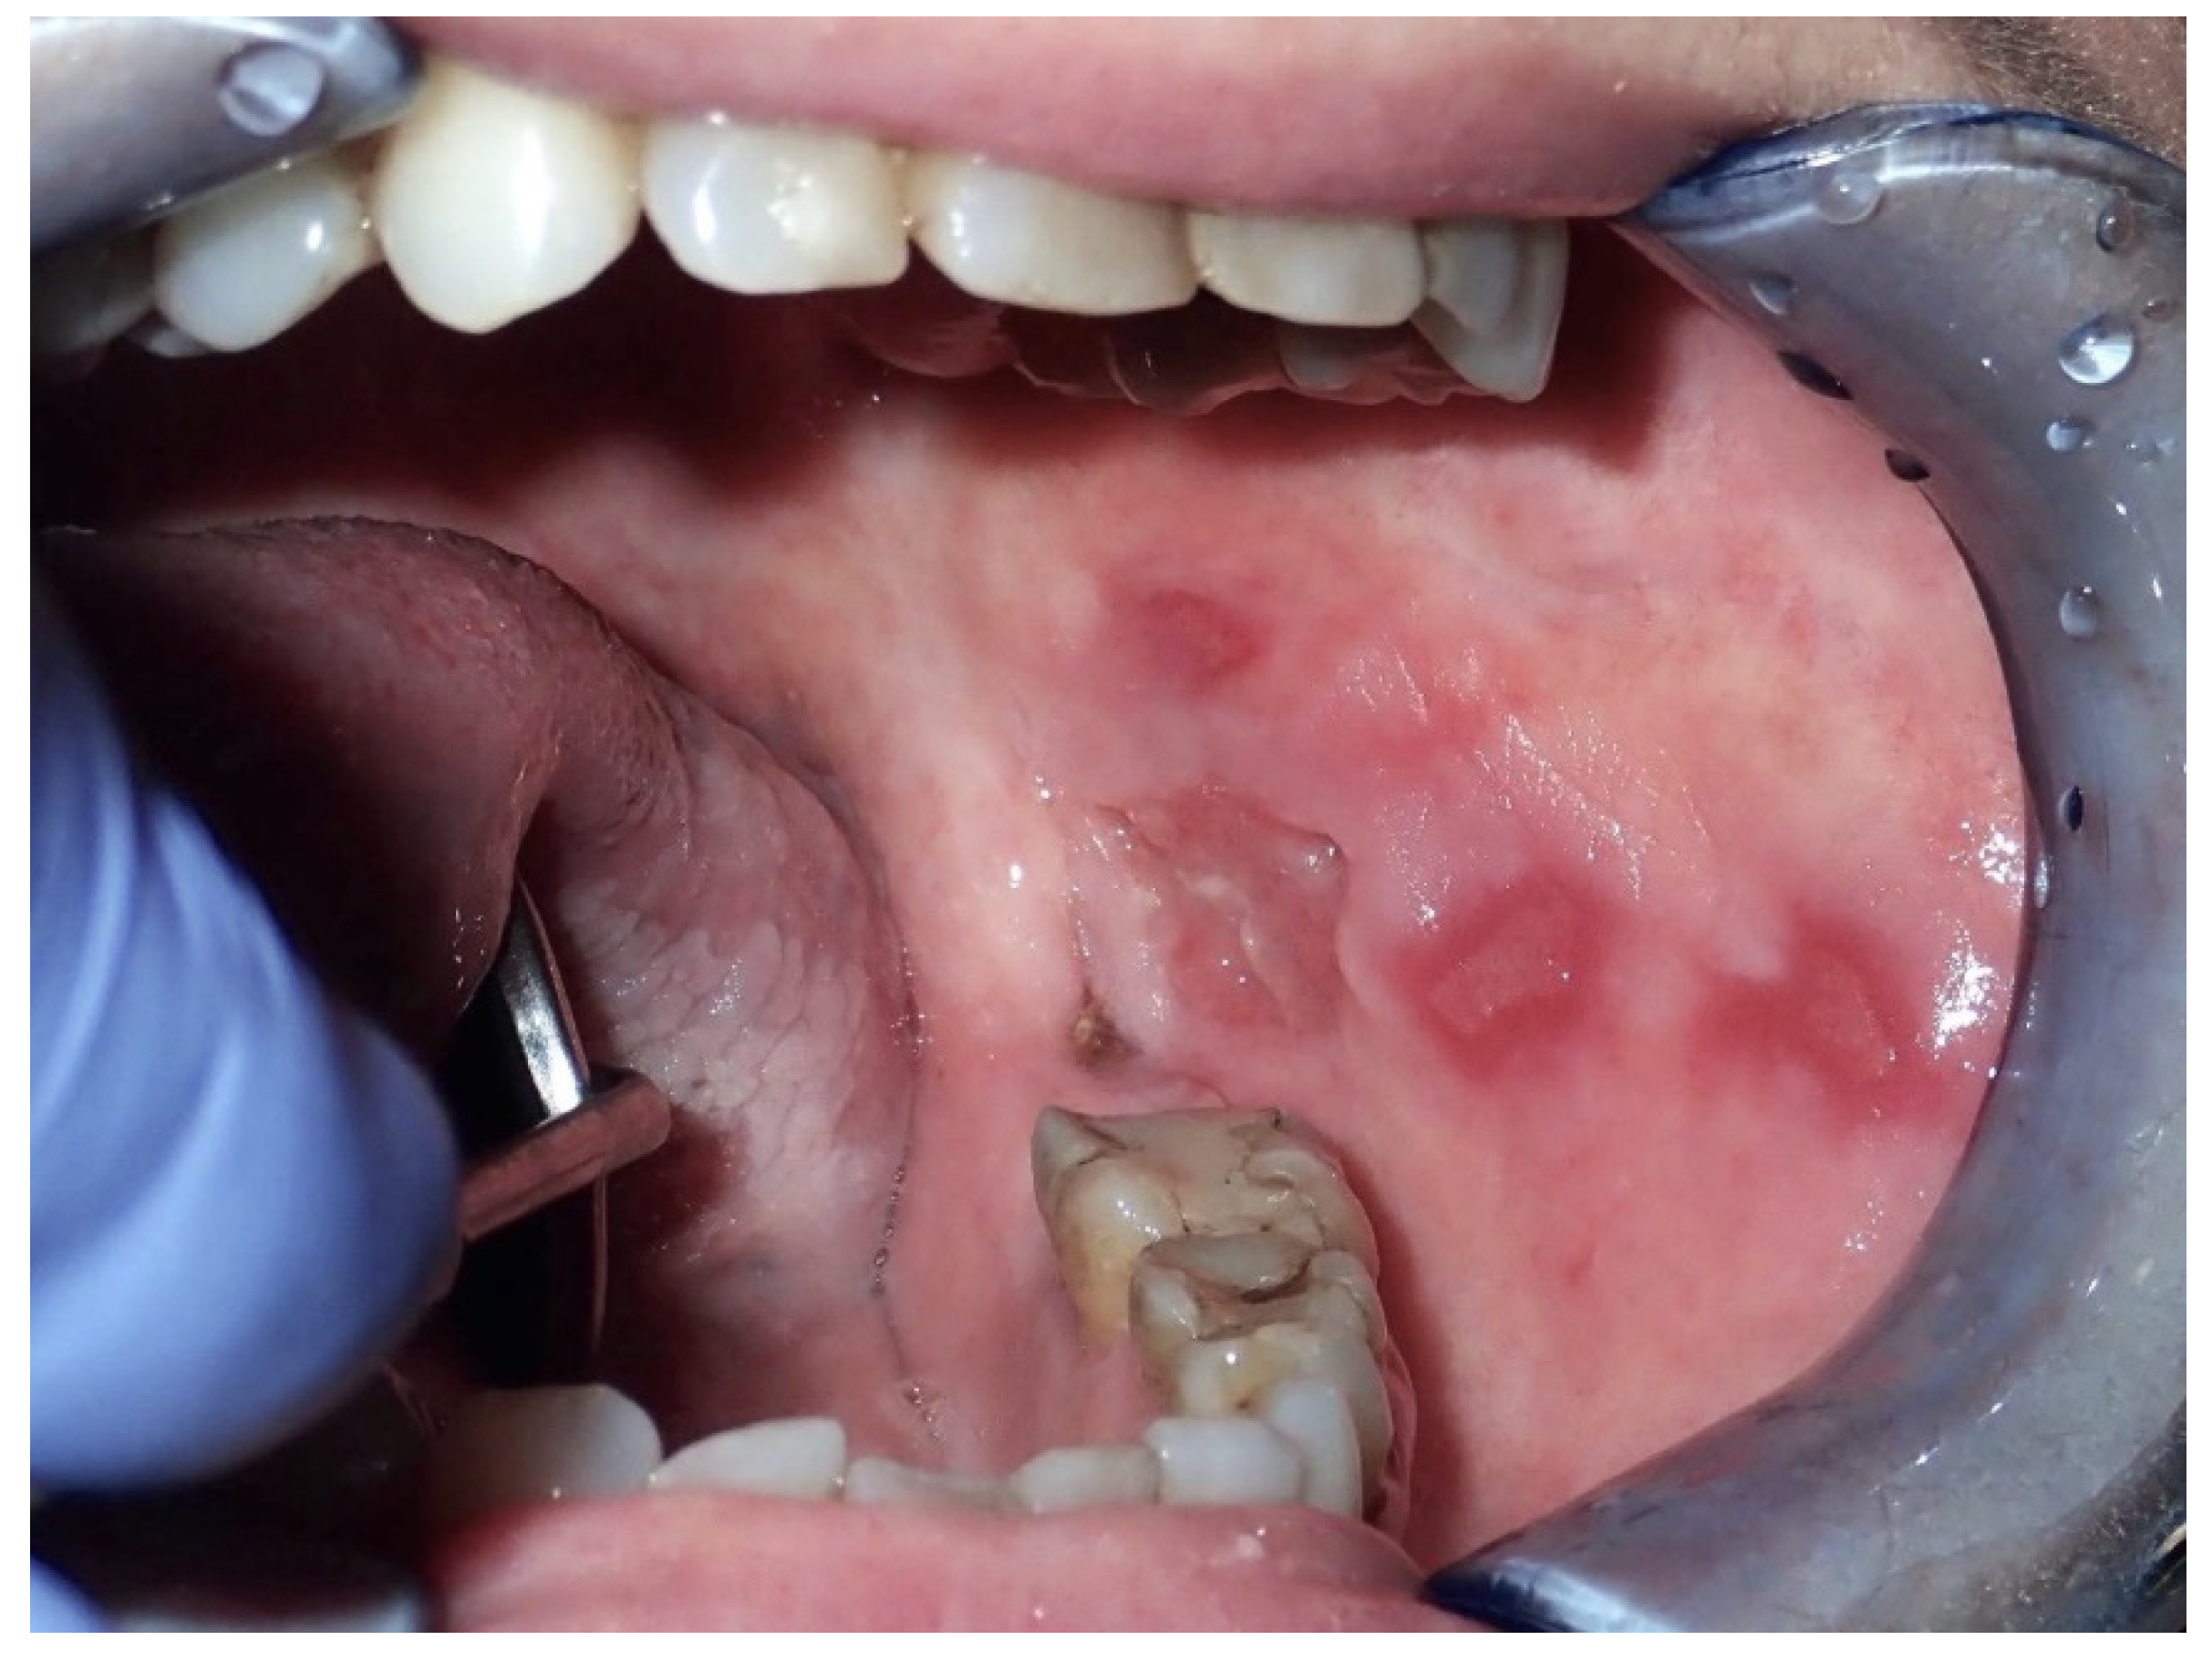

2.2. Erythroplakia

2.3. Oral Lichen Planus